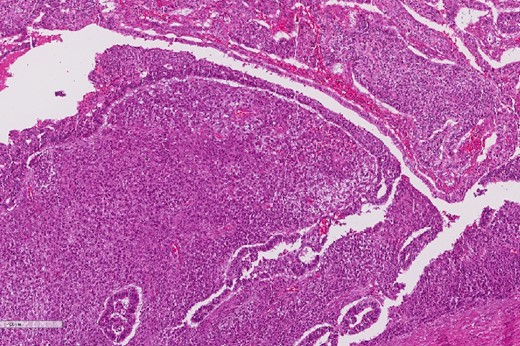

A review of the previously resected esophageal tumor revealed the presence of both epithelial and sarcomatous components. The epithelial component was composed of moderately to poorly differentiated adenocarcinoma, while the sarcomatous component showed hyperchromatic round to spindle cells with scant cytoplasm and frequent mitoses (Figs 3–6). The intrathoracic tumor showed a similar morphology as the sarcomatous component of the esophageal tumor, with focal rhabdomyoblastic differentiation (Fig. 7). The latter was strongly positive for desmin, myogenin, and MyoD1 and was focally positive for synoplastin, CD56, CD 10, and FL1.

The epithelial component of the esophageal tumor is composed of moderately to poorly differentiated adenocarcinoma.